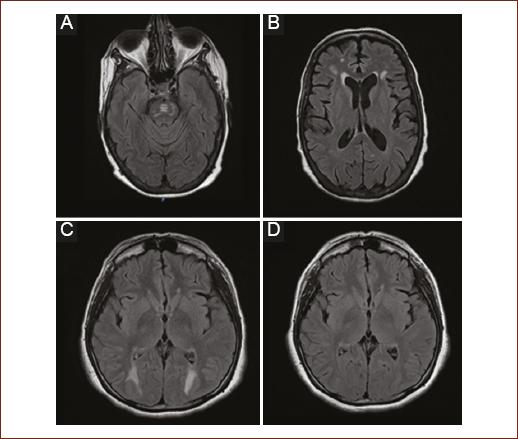

The diagnostic standard is MRI, its indication focuses on moderate-to-severe complications such as in the case of seizures, altered state of consciousness, cortical blindness, and speech alterations. There are no prospective studies of the alterations by imaging, but a predilection for involvement of the white matter in the occipital region has been observed. In post-liver transplant patients, pontine and extra-pontine myelinolysis have also been identified (Fig. 1)12.

Figure 1 Most frequent radiological findings. A: T2 FLAIR sequence: hyperintense lesion in the pontine region corresponding to pontine myelinolysis. B: T2 FLAIR Sequence: multiple intra-axial hyperintense images located diffusely in white matter in relation to leukopathy. C: FLAIR T2 sequence: hyperintense intraxial images symmetrically in the occipital region. D: Control image 3 months later with reversibility of the lesions compatible with posterior reversible encephalopathy syndrome (PRES).